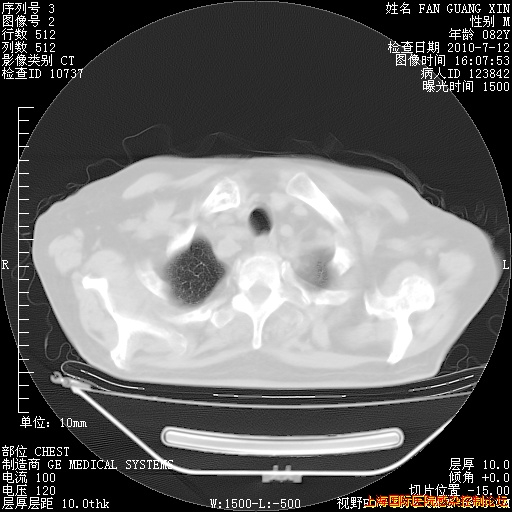

补发6月12日肺部CT肺窗

6月12日肺窗

6月12日纵膈窗